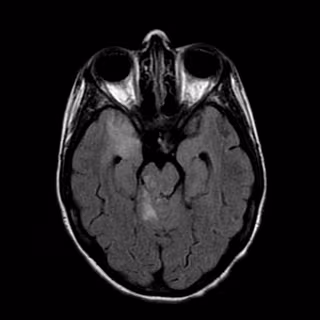

El servicio de urgencias del Hospital Siberia Serena en Talarrubias ha llevado a cabo el primer tratamiento de reperfusión en un paciente con una isquemia cerebral de reciente comienzo, utilizando un sistema de telemedicina específico para este tipo de patologías.

Tras la realización de las preceptivas pruebas de radiodiagnóstico, se procede a la conexión con la Unidad de Ictus a través de un sistema de telemedicina habilitado al efecto en uno de los boxes de la sala de observación.

Desde este punto, la posibilidad de una visión del paciente a través de una cámara de alta definición, permite una estimación del daño cerebral por parte de neurología, así como la valoración de las necesidades terapéuticas del paciente y en los casos en los que sea necesario, la administración de alteplasa (rTPA), glucoproteína capaz de inducir la conversión de plasminógeno en plasmina, y con ello la disolución del coágulo de fibrina causante del daño neurológico, siempre bajo los principios de los protocolos normalizados y preservando el principio de autonomía del paciente y de confidencialidad.